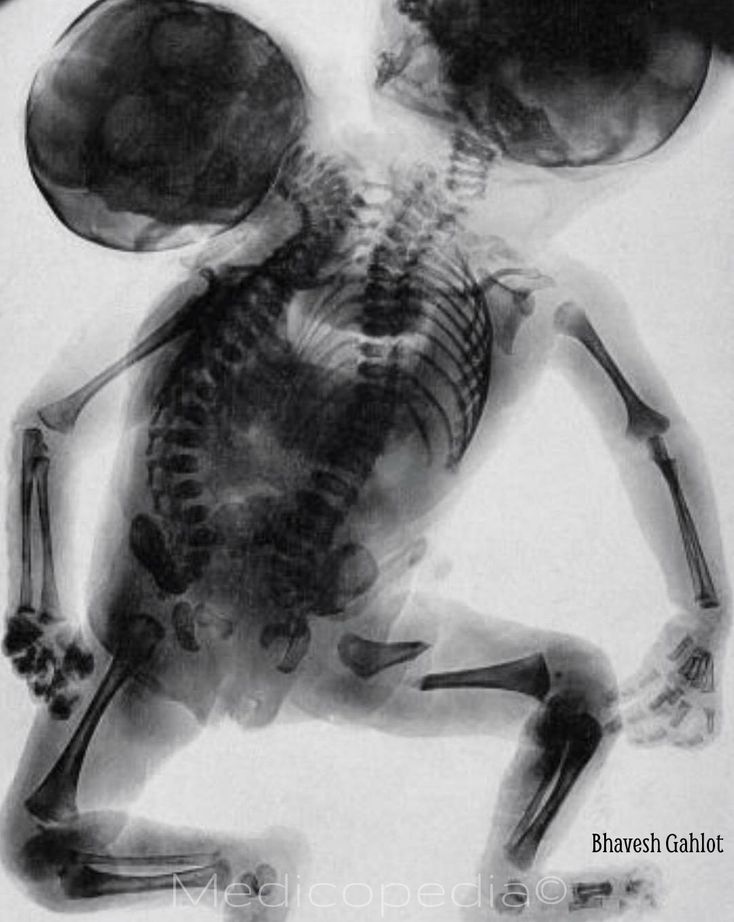

An X-ray of conjoined twins born with two backbones and two heads!! Comment if you’d like to see an actual picture! Conjoined twins are identical twins whose bodies are joined in utero. A rarer form of conjoined twinning, seen here, is the dicephalic parapagus twins which fused side-by-side with a shared pelvis and two separate heads. If carried to term, most dicephalic twins are stillborn, or die soon after birth. Very few survive to adulthood. The extent to which limbs and organs are duplicated varies from case to case. One head may be only partially developed (anencephalic), or both may be complete. In some cases, two complete hearts are present as well, which improves their chances of survival. The total number of arms may be two, three or four. Their prospects are best if no attempt is made to separate them, except in cases where one twin is clearly dying.